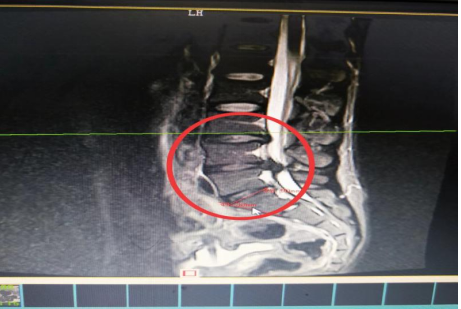

10分鐘后,患者肖先生沒有家屬陪同的情況下被緊急到骨科一區(qū)病房接診滿頭大汗、非常緊張肖先生,舒小林醫(yī)師仔細詢問了病情。原來肖先生從事搬運行業(yè),半年前就腰腿痛就醫(yī)當時在保守治療后稍有緩解,沒有引起重視直到11月13日下午因搬重物后突然感到腰腿劇烈疼痛、麻木、大小便困難,這才120急救電話。骨科一區(qū)錢軍副主任、舒小林醫(yī)師立即給患者作了詳細的體查,并立即聯(lián)系做急診腰椎磁共振確定有無神經(jīng)受壓。腰椎磁共振結(jié)果提示:腰4/腰5椎間盤膨出,導(dǎo)致馬尾神經(jīng)嚴重受壓,有明顯的手術(shù)指征,如不盡快手術(shù)會致神經(jīng)受損難以恢復(fù)。錢軍副主任來到肖先生病床前,將手術(shù)方案、手術(shù)風險及并發(fā)癥詳細告知肖先生本人,肖先生表示同意并簽字馬上手術(shù)。

晚上23點肖先生在全麻下行腰椎后路孔鏡下腰4椎板切除、腰4/5脫出髓核摘除、神經(jīng)根管擴大成形、神經(jīng)根粘連松解手術(shù)。手術(shù)過程順利,術(shù)后返回病房時,肖先生下肢便能夠抬腿民。術(shù)后第二天蘇光輝主任、錢軍副主任帶領(lǐng)醫(yī)師團隊查房,肖先生非常開心地告訴醫(yī)師“我現(xiàn)在腰不痛了、腳也不麻了,還能自行到床邊上廁所了。感謝,感謝各位醫(yī)師專家妙手回春,感謝護理團隊的悉心照顧”。連夜趕來醫(yī)院的媽媽也樂呵呵地說:“我代表全家感謝你們!并鄭重地為醫(yī)務(wù)人員一面錦旗。目前肖先生恢復(fù)良好,已于術(shù)后5第五天康復(fù)出院了。